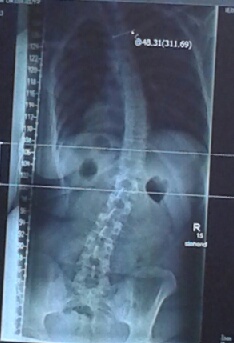

Dateianhänge

13725708992581.jpg

13725708992581.jpg (27.56 KiB) 16536 mal betrachtet

was an deiner Krümmung "außergewöhnlich" ist, ist die Form eines C. Die meisten Skoliosen haben die Form eines S. Aber so selten ist die C-Form auch wieder nicht.

Von deinem Röntgenbild fehlt leider der Abschnitt der Halswirbelsäule, dann könnte man das Röntgenbild besser beurteilen, aber so viel fehlt auch wieder nicht.